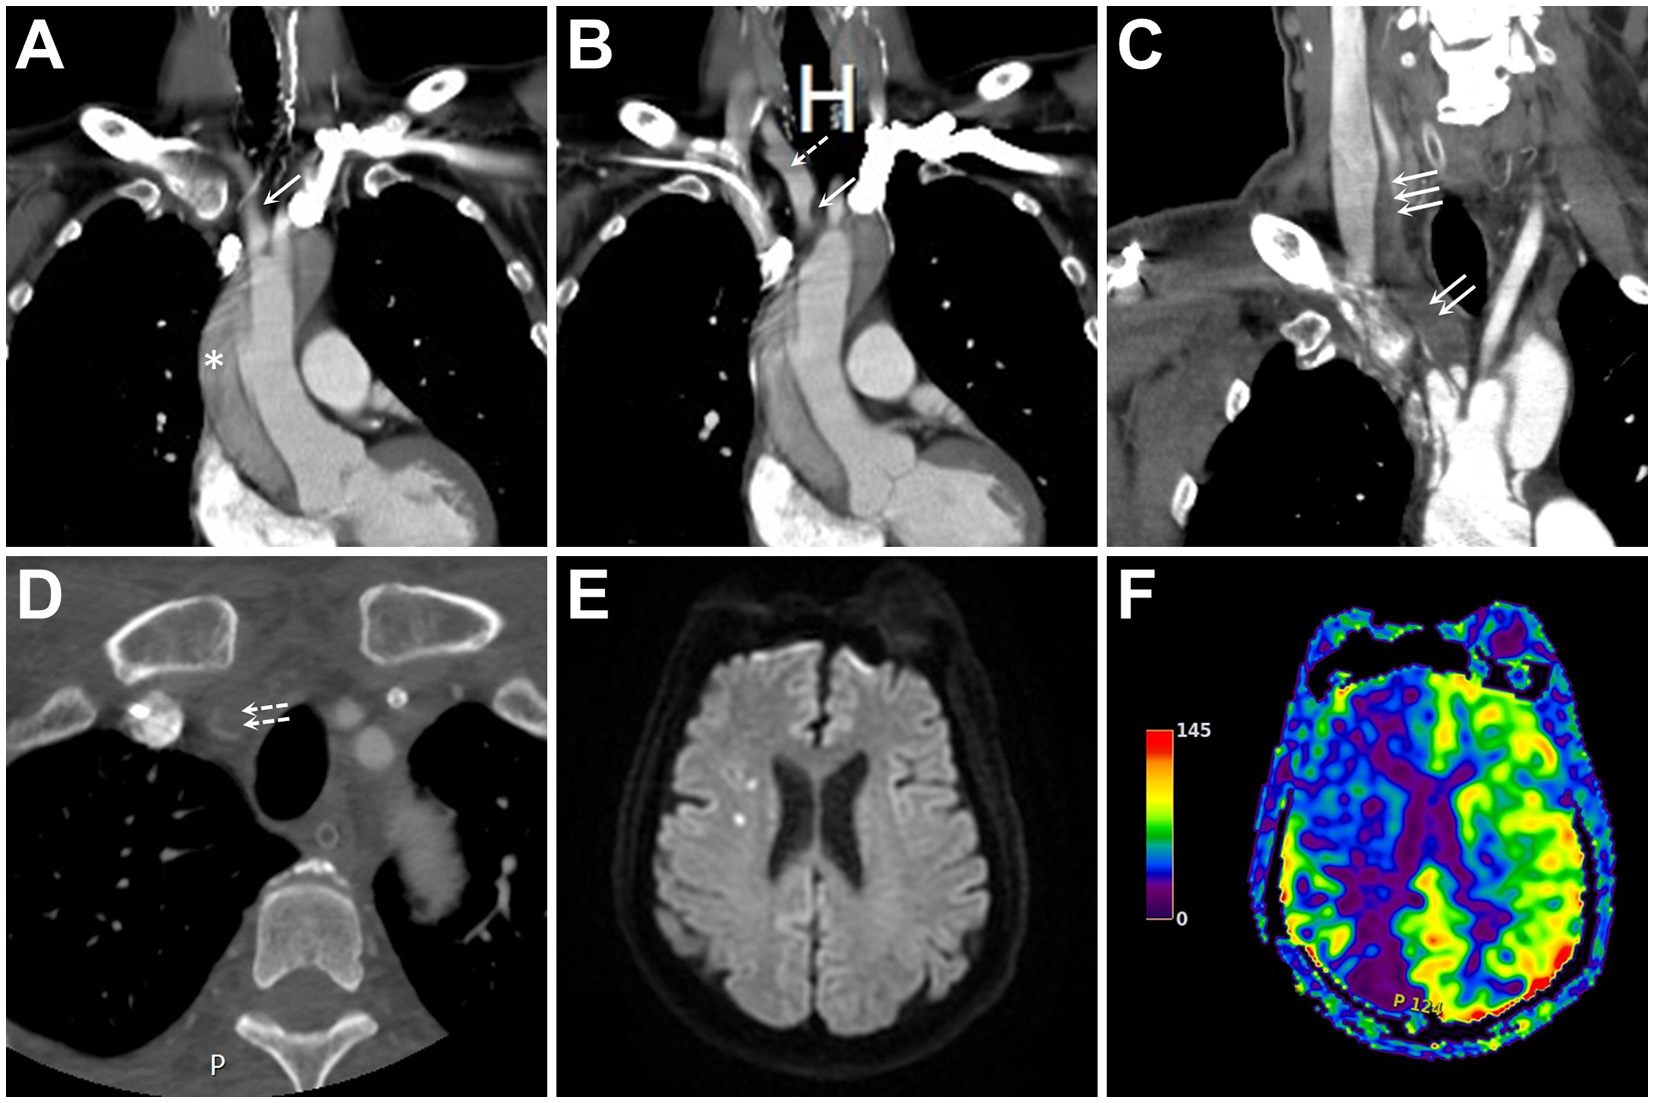

Figure 1

(A, B) Initial contrast-enhanced computed tomography (CECT) of the neck and chest in two consecutive coronal sections show an aortic dissection (asterisk) with innominate artery (IA) extension (single solid arrow). At this point, the main IA trunk remained patent without flow-limiting stenosis (single dashed arrow). (C, D) Coronal (C) and axial (D) images of CECT two days following ascending aortic grafting show expansion of the dissection's false lumen (double solid arrows), the distal extension of the dissection involving common carotid artery (triple solid arrows) and subclavian artery (double dashed arrows), and nearly complete occlusion of the main IA trunk and its bifurcation. (E, F) Diffusion-weighted imaging and arterial spin labeling perfusion magnetic resonance imaging of the brain reveal few embolic spots (E) associated with a large hypoperfusion in the right hemisphere (F).

The patient recovered well immediately after the operation. On postoperative day 2, the patient became lethargic, and his blood pressure in the right arm dropped to ~50/40 mmHg. CECT of the neck revealed a progression of the IA dissection, tight narrowing of the residual IA true lumen, and involvement of the right CCA and subclavian artery (SA) orifices (Figures 1C, D). Perfusion magnetic resonance imaging of the brain showed marked right-sided hemispheric hypoperfusion (Figures 1E, F).